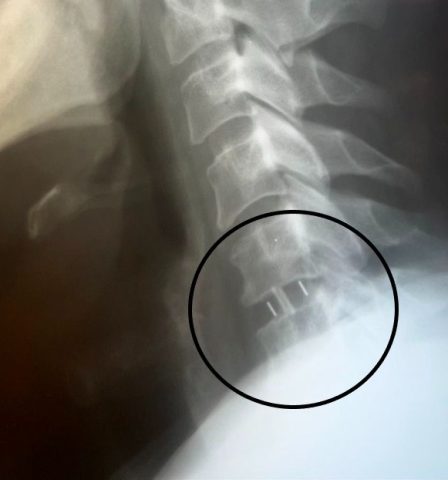

Медики пояснили: если не удалять грыжу, правую руку может парализовать. Нейрохирурги Владимир и Евгений Дроновы удалили межпозвонковый диск и грыжу с использованием операционного оптического прибора, микрохирургической техники и инструментария. Врачи устранили и компрессию спинного мозга и нервных корешков. Также между двумя соседними позвонками установили межтеловой кейдж – металлическую конструкцию, которая соединила позвонки между собой.